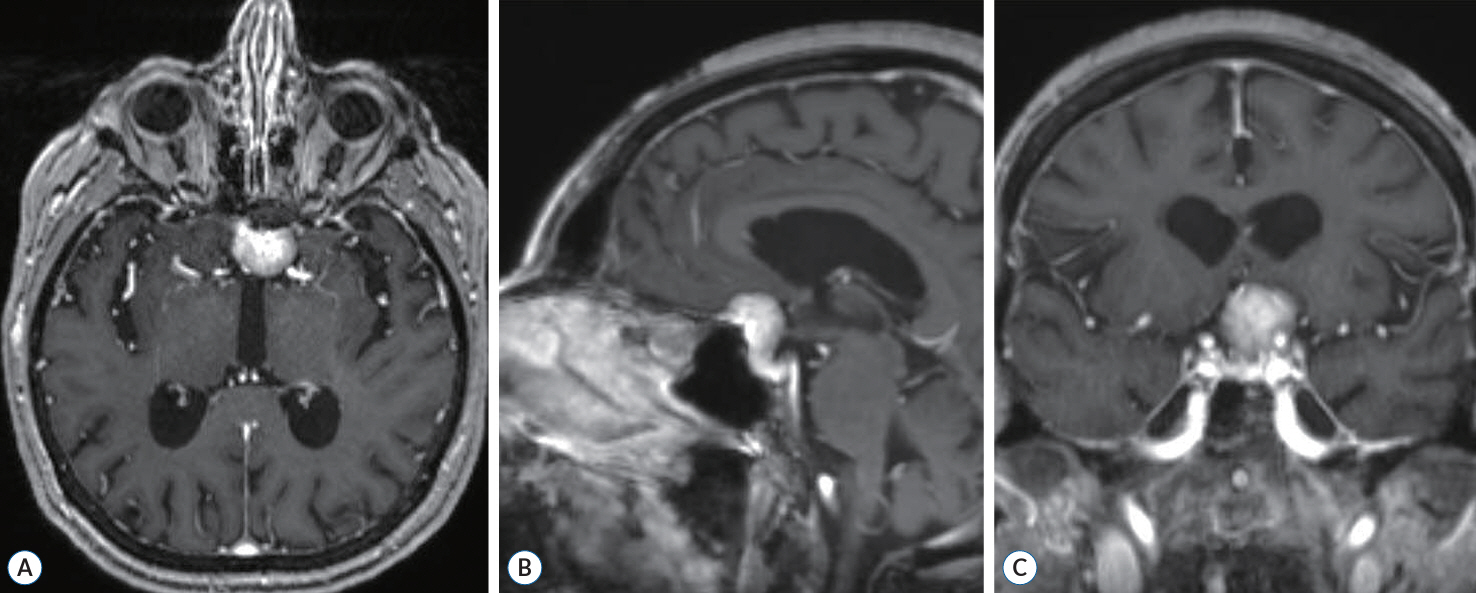

A Successful Control of the Intraoperative Bleeding from McConnell’s Artery during Fully Endoscopic Resection of Planum Sphenoidale Meningioma Using Bone Chip and Bioglue : A Case Report

- The endoscopic transsphenoidal approach is a common approach used in skull base neurosurgery to reach the sellar region. One of the intraoperative risks of this approach is intraoperative bleeding out of the carotid artery. Gentle drilling can prevent carotid artery injury. However, injury to smaller branches, such as the McConnell’s capsular artery, which is located within the surgical corridor, is more difficult to prevent. If such an injury is within the junction to the main trunk of the carotid artery, there will be a small circular defect in this area. This can result in massive blood loss and should be closed surgically immediately. We describe a clinical case of intraoperative bleeding from the McConnell’s artery originating from the carotid arterial segment (C4) in a 78-year-old female patient operated on for planum sphenoidale meningioma via endoscopic transsphenoidal approach, as well as provide a technical note on a possible technique for bleeding control in such cases. Pinpoint carotid bleeding as a result of intraoperative injury can be stopped by wedging a bone fragment in the carotid canal and fixing it in that position with histoacryl glue at the defect site.